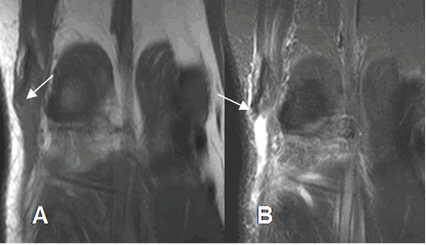

Fig 63. Ruptura muscular.

A: RM coronal en T1 y B: RM coronal en STIR. Ruptura retraída, en el tendón del bíceps femoral.